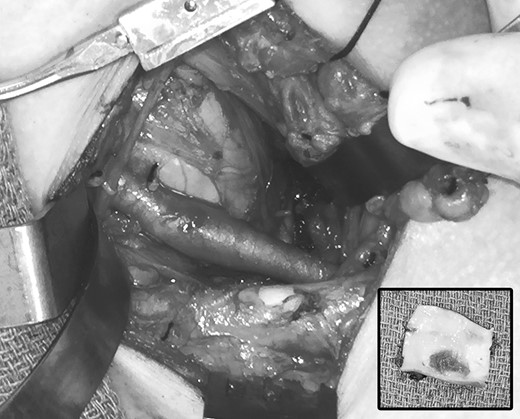

Clinical evaluation revealed an absence of palpable pulses at the left wrist but adequate arterial circulation to the hand at rest, with brisk capillary refill in the fingers and no signs of digital embolism. Upper extremity strength, sensation and range of motion were normal and there were no signs of swelling, edema or cyanosis to suggest venous obstruction. The patient was brought to the operating room for thoracic outlet decompression using a left supraclavicular approach. After mobilizing and rotating the scalene fat pad on a lateral pedicle, the phrenic nerve was identified in its expected position on the surface of the anterior scalene muscle; however, the subclavian artery was not found within the scalene triangle adjacent to the brachial plexus, but in front of the anterior scalene muscle insertion on the first rib, in the costoclavicular space directly posterior to the phrenic nerve (Figs 4 and 5). Thoracic outlet decompression was performed with anterior and middle scalenectomy, brachial plexus neurolysis and first rib resection [10]. Direct inspection and intraoperative left upper extremity arteriography demonstrated post-stenotic dilatation of the subclavian artery and chronic occlusion of the brachial artery with abundant collaterals. The affected segment of the subclavian artery was resected and found to contain an ulcerated lesion with thrombus (Fig. 6), and the artery was reconstructed with a 6-mm diameter cryopreserved femoral artery interposition graft (Fig. 7). The patient was discharged on postoperative Day 3 taking a direct oral anticoagulant and she was clinically stable during subsequent follow-up.

Operative photograph demonstrating initial exposure of the left supraclavicular space, with the scalene fat pad mobilized and rotated laterally. The subclavian artery was found in the costoclavicular space in front of the anterior scalene muscle.

Close-up view of the subclavian artery and related structures. ASM, anterior scalene muscle; BP, brachial plexus; EJV, external jugular vein; IJV, internal jugular vein; PhN, phrenic nerve; MSM, middle scalene muscle; SCA, subclavian artery; SCV, subclavian vein.

Operative photograph after thoracic outlet decompression, demonstrating area of post-stenotic dilatation in the left subclavian artery. Inset, excised segment of the affected left subclavian artery, demonstrating ulceration and thrombus on the luminal surface.